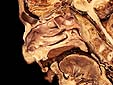

Pared Lateral de las Fosas Nasales